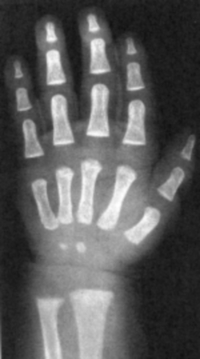

Sexo Masculino

1 ano

1 ano e 3 meses